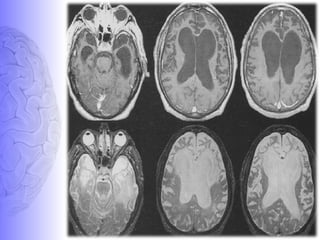

MRI features of FTD

• MR features:

 Severe sharply localized atrophy- bilaterally symmetric-

“knife-blade atrophy.”

 Hyperintense signal in the cortex and underlying white

matter of the affected areas.

• Areas involved: frontal lobe, anterior temporal lobes,

extra pyramidal nuclei especially the caudate nucleus,

insular cortex & anterior corpus callosum.

• Areas spared: Posterior two thirds of the superior

temporal gyrus, occipital lobes, parietal lobes &

perirolandic region

• These MR findings in an appropriate clinical setting

may support the diagnosis of FTD.

Frontotemporal dementia